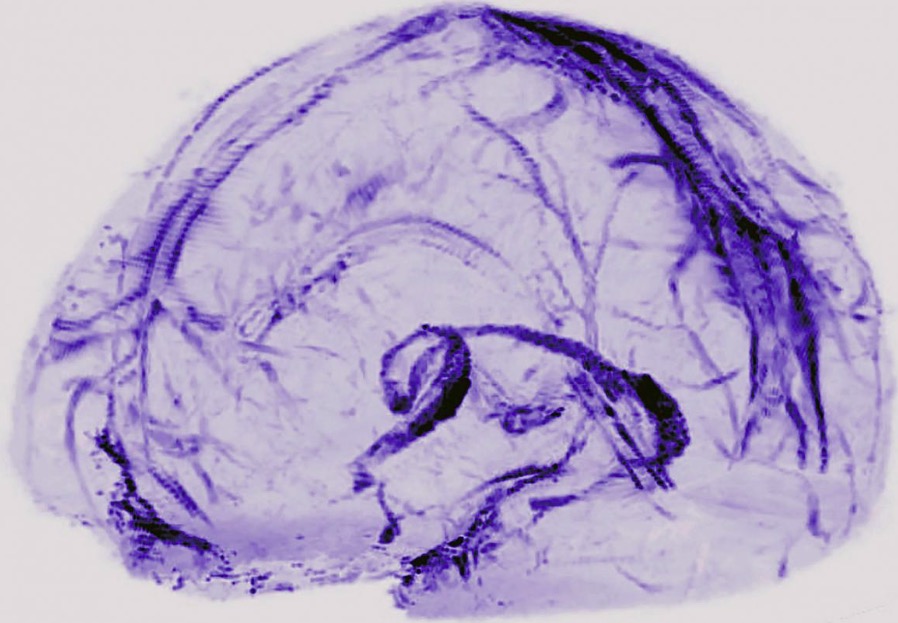

Vous pouvez voir ci-dessous un modèle 3D de ce système de drainage :